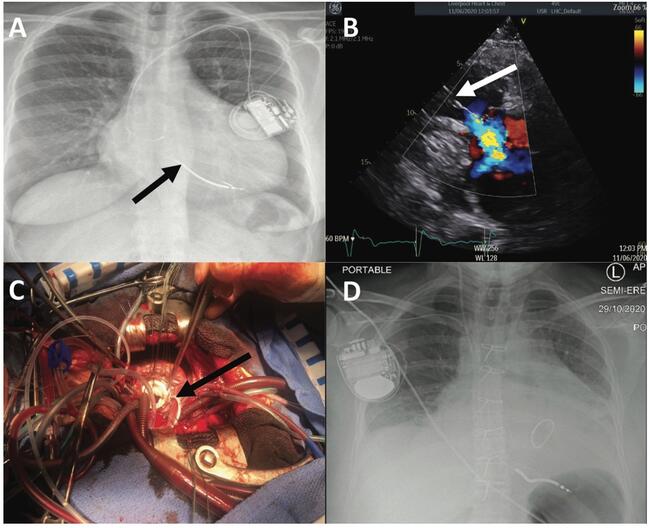

Management of Iatrogenic Severe Tricuspid Regurgitation: Hybrid Lead Extraction and Paravalvular Insertion of a New ICD Lead

1535-2226

Tricuspid regurgitation (TR) caused by iatrogenic implantation of pacing wires is an uncommon but significant complication of transvenous pacing.1 We present a case of severe symptomatic TR due to right ventricular (RV) leads, in a patient with hypertrophic cardiomyopathy (HCM) and concomitant left ventricular outflow tract (LVOT) obstruction with mitral valve (MV) regurgitation. A hybrid procedure was undertaken with percutaneous lead extraction, septal myomectomy, MV repair and replacement of the tricuspid valve, and insertion of a paravalvular implantable cardioverter-defibrillator (ICD) lead to prevent further iatrogenic TR.